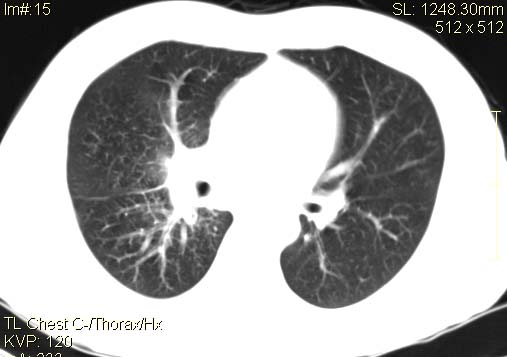

以下是引用qc80012345在2007-4-17 12:33:00的发言:[br]右肺下叶周围型肺癌伴肺门及纵隔内淋巴结转移;比较清楚。

以下是引用qingyuan在2007-4-17 14:19:00的发言:[br]右肺下叶外侧后段胸膜下区节结样病变、分叶、内可见空洞,壁厚薄不均,胸膜凹陷、肺门周围区纹理增粗、僵硬、并近似小结节样改变,肺门区软组织节结、纵膈淋巴结肿大,患者病史长、抗炎治疗无好转炎性改变基本排除,考虑:右肺下叶周围型肺癌伴纵膈及右肺门区淋巴结转移、肺内淋巴管受侵。